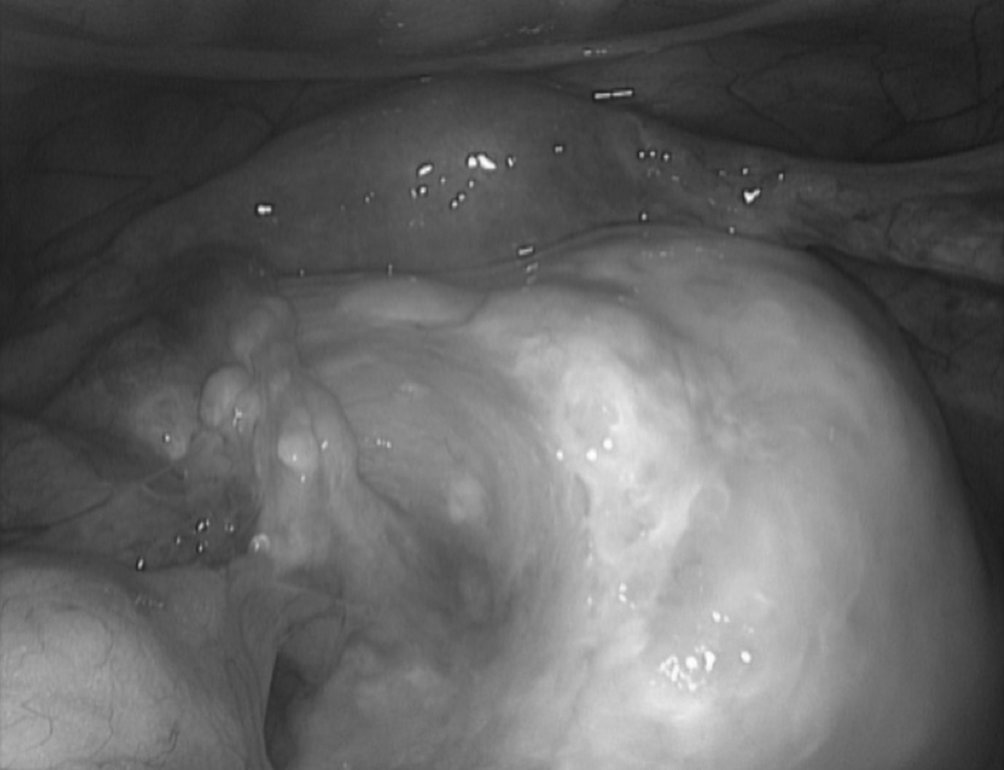

Figure 19.1 Vue en cœlioscopie du pelvis visualisant un petit utérus de taille normale et au premier plan un volumineux kyste ovarien d’allure organique avec une corticale ovarienne lisse sans végétation ni anomalie de la vascularisation de la corticale ovarienne en faveur de la bénignité

Figure 19.1 Vue en cœlioscopie du pelvis visualisant un petit utérus de taille normale et au premier plan un volumineux kyste ovarien d’allure organique avec une corticale ovarienne lisse sans végétation ni anomalie de la vascularisation de la corticale ovarienne en faveur de la bénignité.